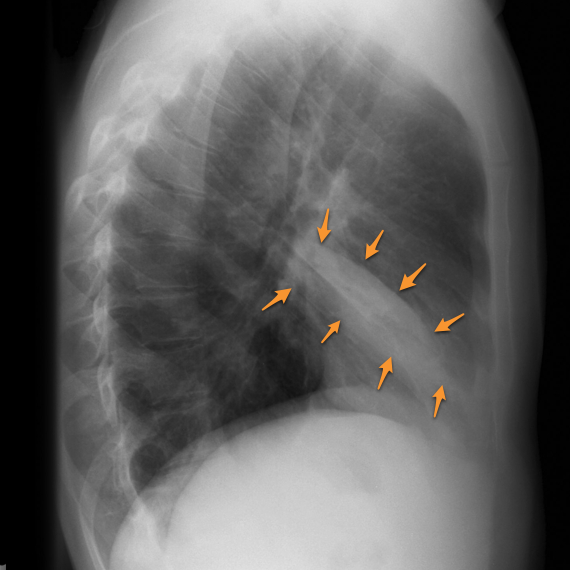

Right middle lobe atelectasis

The findings of right middle lobe atelctasis can be subtle on the frontal radiograph. Silhoutting of the right heart border by the collapsed medial segment of the middle lobe may be the only clue. The lateral radiograph shows a wedge-shaped opacity anteriorly.